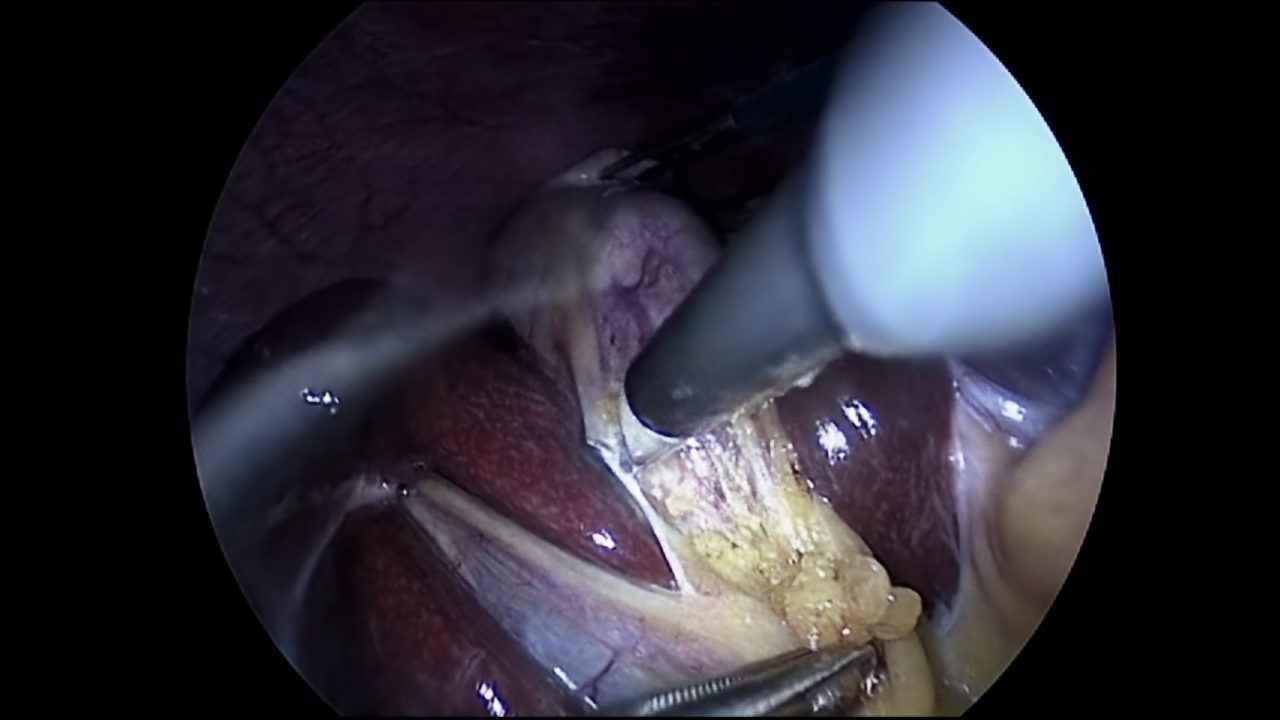

Although the visualisation for 300 epochs is already capable of presenting numerous details, the NeRV-S model was also trained for 1200 epochs. With this next model, it is possible to compare how much the quality of the image can be improved based on the number of epochs. The visualisation for 1200 epochs is presented in Figure 5.

Figure 5: Ground truth (left) (Twinanda et al., 2017) and prediction (right) of NeRV-S (1200 epochs) for frame 10.

Using the comparison between Figures 4 and 5, it can be stated that the image quality improved with the increased number of epochs. However, this difference can be best observed with great zoom. For this reason, Figure 6 has been provided, where a small glare on one of the tools in the left part of the image is examined. Based on this figure the comparison between ground truth and NeRV-S model for 1200 and 300 epochs can be visualised.